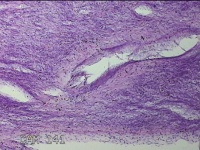

子宫体肌瘤结节

性别

女

年龄

32岁

临床诊断

子宫肌瘤 疤痕子宫

一般病史

发现子宫肌瘤数月余。

标本名称

大体所见

灰白色圆柱形条索状组织10x7.5x1.8㎝一堆,切面均为灰白色结节状或编织状,质中。

图1